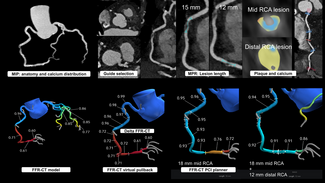

Therapy with 325 mg aspirin, loading 600 mg clopidogrel, and 5.000 IU unfractionated heparin was started, and the patient was immediately transferred to the catheterization laboratory. Coronary angiography showed total occlusion of mid left anterior descending (LAD) coronary artery, with thrombolysis in acute myocardial infarction (TIMI) 0 flow as shown in Figure 2. After vessel  wiring through an Extra Back Up 6 Fr guiding catheter (Medtronic), an aspiration catheter (6 Fr Export AP; Medtronic) was inserted. The blood clot was successfully aspirated with immediate relief of pain and resolution of ST segment elevation. TIMI III flow was restored with no residual lesions at the site of thrombus or the distal parts of the vessel (Figure 3). A decision was made not to deploy a balloon or a stent in the affected area. Left circumflex and right coronary arteries were normal, as detected 1 year before.

A transthoracic echo followed by transesophageal echo obtained after the coronary procedure in the coronary care unit showed a 2.5 cm visible movable thrombus over the atrial surface of the mechanical mitral valve (Figure 4), and almost normal systolic left ventricular function with mild apical hypokinesia. Levels of troponin T and CK were actually raised up to 4.8 ng/mL and 900 IU/L, respectively. The patient was commenced on heparin continuous IV infusion, and a cardiothoracic reintervention was performed 1 week later, confirming the existence of a voluminous thrombus over the prosthetic mitral valve and proceeding in a replacement of the thrombosed valve. Although surgery was technically considered high risk due to a recent history of MI, considerable valve thrombus burden discouraged other non-surgical approaches. Actually, 6 months later, the patient is asymptomatic with normally functioning mitral valve prosthesis.

Coronary embolism usually affects the left coronary system, particularly the LAD. Pesendorfer et al,4 using an in vitro model, found that embolism happens due to active suction of blood/thrombus into the coronary artery at the onset of diastole, at the level of aortic valve. Since the left coronary artery is larger than the right one, a greater proportion of flow is received by the left one, hence, more emboli. Because of the direct downward course of the LAD, it may be more liable to embolization than the left circumflex artery, which is at a right angle to the main trunk.5 In our case, the patient had a totally occluded LAD, and we confirmed the mitral valve as the source of embolus (Figure 4). In all previously reported cases,6-8 a source of embolus was not evident, making the diagnosis of embolic acute MI rather presumptive.